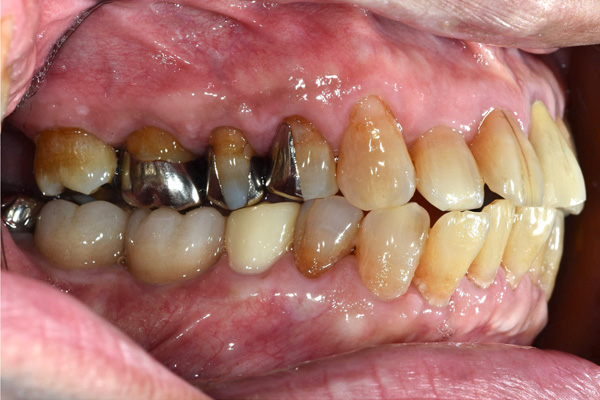

BEFORE

AFTER

| 年代・性別 | 50代 男性 |

|---|---|

| 主訴 | 右上下の歯が痛い |

| 治療期間 | 約12ヶ月 |

| 費用 | 2,500,000円 |

| 治療内容 | インプラント、骨造成、結合組織移植、セラミック修復 |

| 治療に伴うリスク | インプラント周囲炎 セラミックの破折、脱離 |